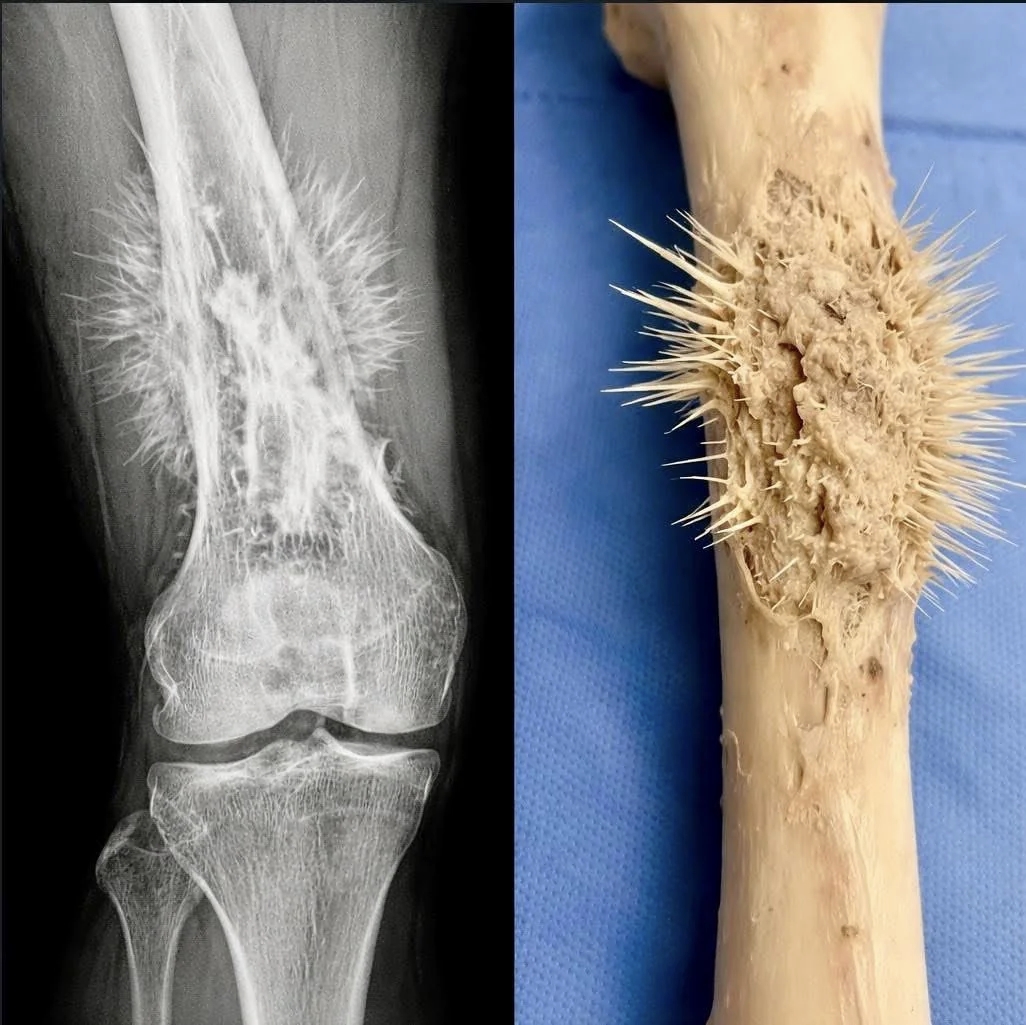

¸¹À̵é ÀذíÀÖ´ÂÁ¡ : ÂïÈù »À°¡ Åë°·Î ³ª¿ÍÀÖ´Ù. °ñÀ°Á¾Àº º¸Åë û¼Ò³â±â È£¹ßÇÑ´Ù ¤Ð¤Ì [1]

¸¹À̵é ÀذíÀÖ´ÂÁ¡ : ÂïÈù »À°¡ Åë°·Î ³ª¿ÍÀÖ´Ù. °ñÀ°Á¾Àº º¸Åë û¼Ò³â±â È£¹ßÇÑ´Ù ¤Ð¤Ì